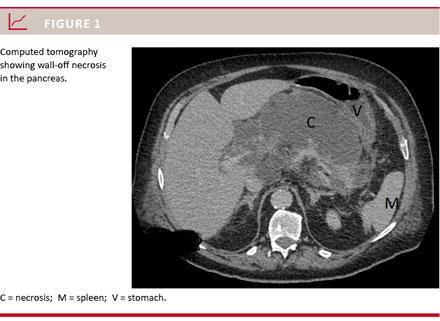

The corner stone in the treatment of severe acute pancreatitis is supportive care, which can include ventilator therapy, dialysis and parenteral nutrition. Necrosis of the pancreas/peripancreatic tissue is often seen in these severe cases (Figure 1). There is consensus

that infected necrosis should be removed by drainage/necrosectomy, but intervention on sterile collections is also recommended if the patient has ongoing organ failure, abdominal compartment syndrome, ongoing gastric/intestinal/biliary outlet obstruction, persistent symptoms or disconnected duct syndrome with persisting symptomatic collection(s) [2]. The methods and the timing of drainage/necrosectomy have changed over the years. Thus, laparotomy with subsequent continuous rinsing via drains or laparostomy with repeat necrosectomy used to be the dominant methods. Currently, intervention is often sought accomplished by less invasive procedures such as external ultrasound-guided drainage. In case of therapeutic failure this can then be followed by transgastric necrosectomy performed either by endoscopy or by laparoscopy/-tomy (the step-up approach) [3]. Regardless of the procedure chosen, it should not be performed within four weeks after the onset of the disease in order to make the necrosis encapsulate.